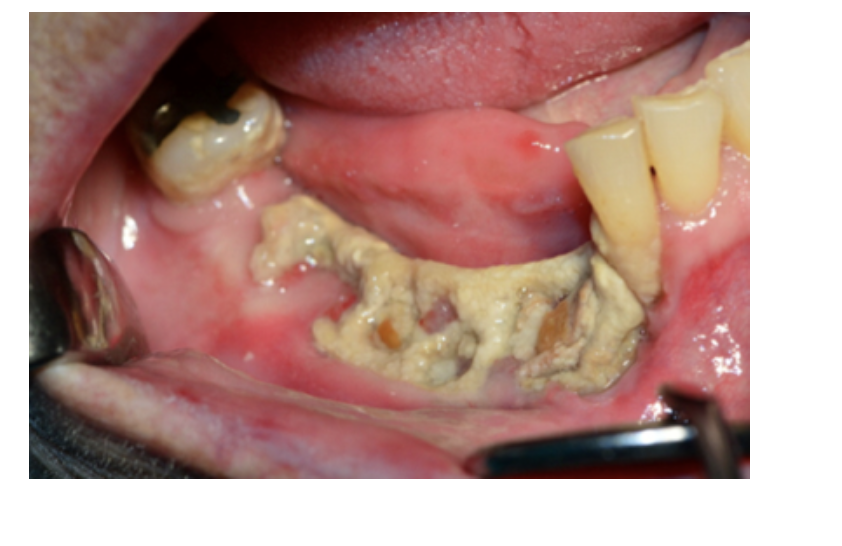

Bisphosphonate Related Osteonecrosis of the Jaws (BRONJ)

A

Greater risk w/IV Bisphosphonates than oral

5 yr survival rate: 25-40% (Pretty deadly)

Jaw Pain

* exposed necrotic bone

Tx: CHX rinse, antibiotics, conservative sx